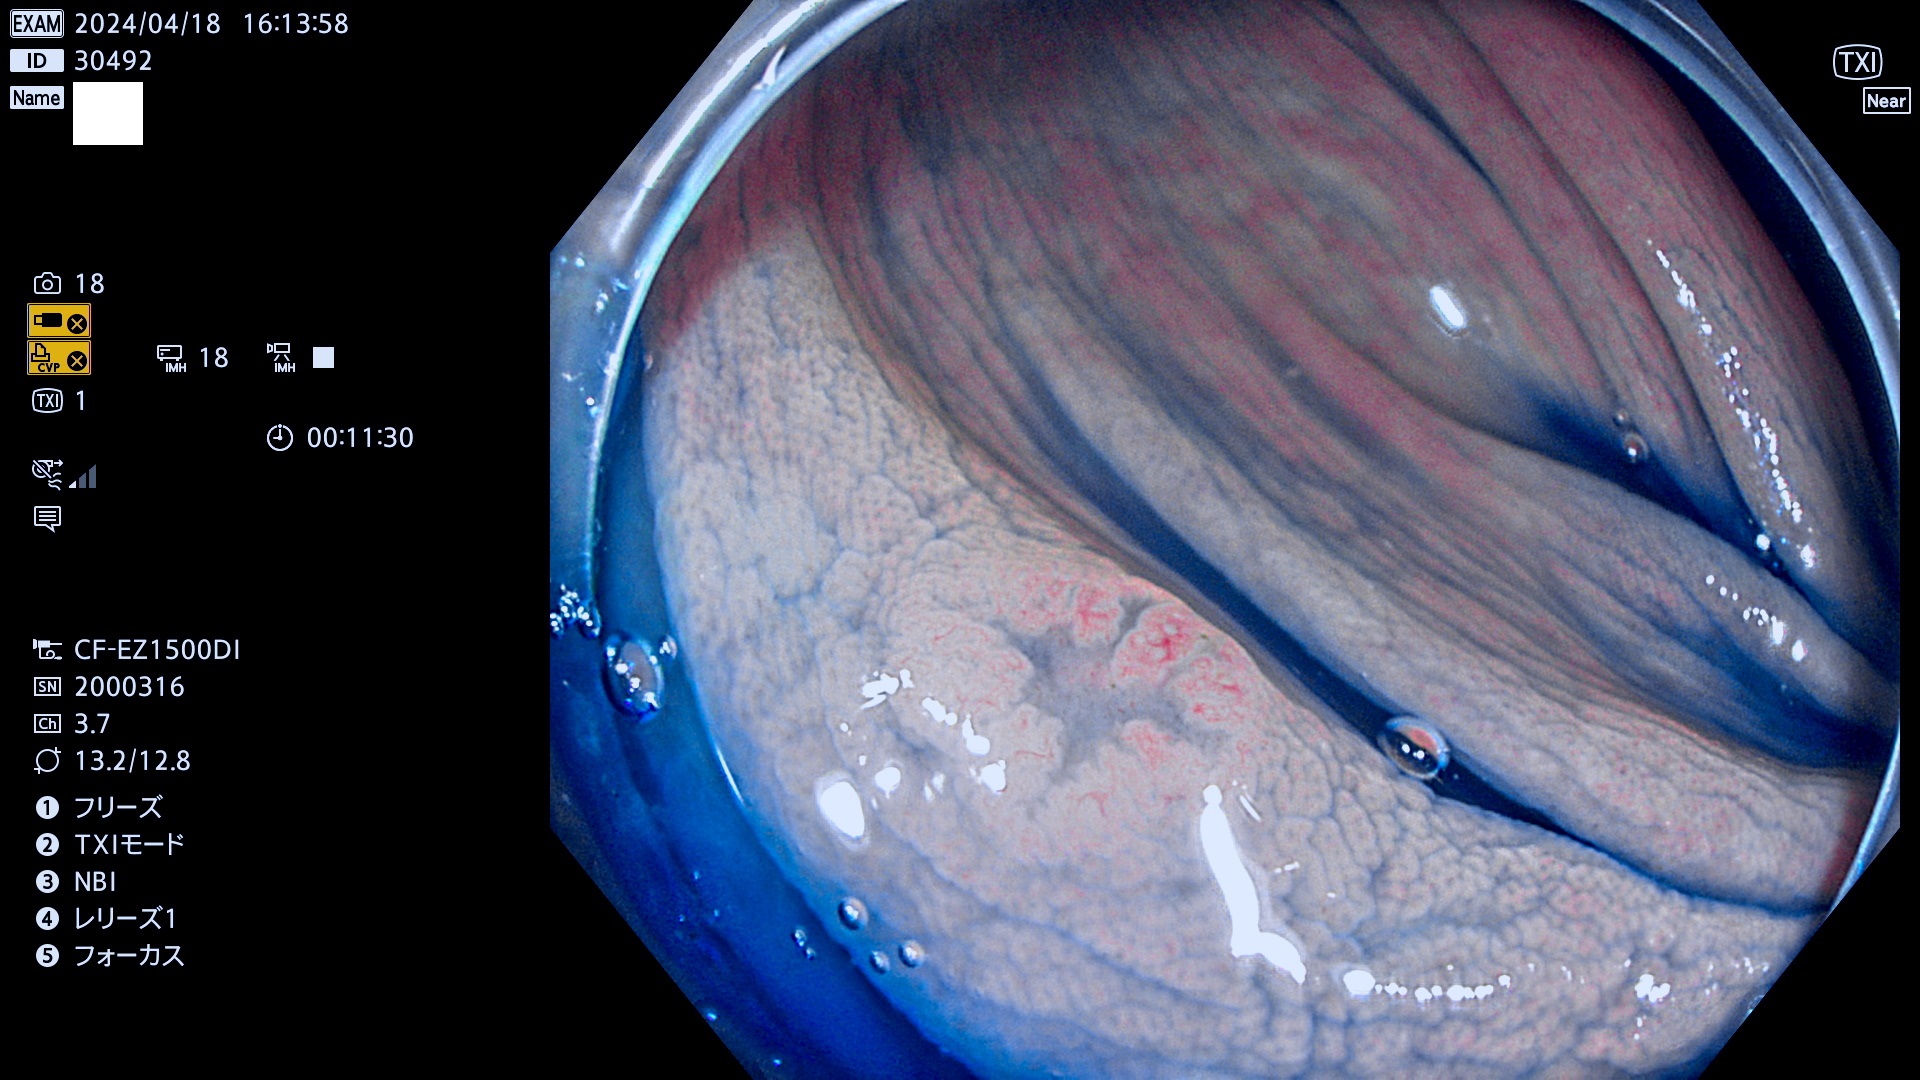

表面型腺腫(Flat Adenoma)の中で、完全に平坦な物をUb、陥凹している物をUcと呼びます。平坦隆起型(Ua)よりも、発見が難しく危険な病変です。

毎週の検査(木・金・土・日)に発見されたUb、Uc型・腺腫を、その週の日曜の夜にUPし1週間、提示します。

抽出の対象期間 2024年4月18日〜4月21の4日間(40件の検査)3件 (3/40=8%)